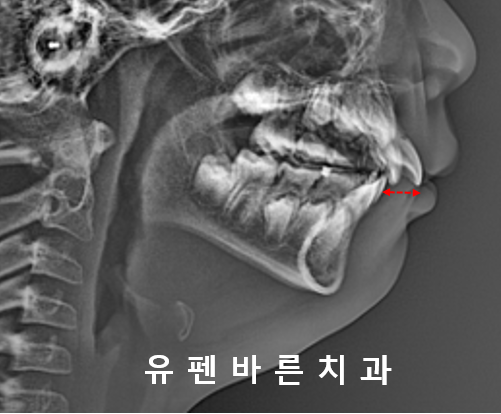

먼저

1차교정, 소아교정을 위해

옆모습 엑스레이를 찍어보았어요

아랫니에 비해 윗니들이

앞으로 뻐드러져 있고

윗니와 아랫니 사이의 공간이

꽤 컸는데요!